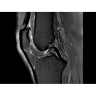

• РЧ-катушки, оптимизированные для исследования конкретных участков тела — элементы катушек высокой плотности располагаются вокруг исследуемых участков тела и при необходимости обеспечивают расширенный охват и оптимальное качество изображений при каждой процедуре.

• Широкое поле зрения — поле зрения шириной 50 см позволяет охватывать крупные анатомические области за меньшее число сканов.

МР-томограф Optima MR450w с диаметром туннеля 70 см обеспечивает более комфортные условия для пациентов, в первую очередь, для полных людей, детей и лиц, страдающих клаустрофобией. При этом повышенное удобство для пациентов обеспечено не только нешироким туннелем — клинические приложения нового поколения сокращают продолжительность исследований, а улучшенный поток воздуха обеспечивает удобный микроклимат во время исследования.